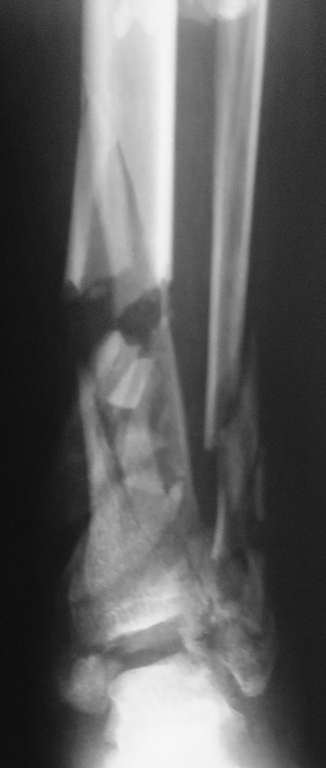

Перелом пилона

Пациент, 22 года, травму получил в результате ДТП (управление мотоциклом). Имеет место открытый оскольчатый перелом костей левой голени в нижней трети.Хотелось бы узнать Ваши мнения по лечению данного пациента.

То примеры, а то практика. Конверсия аппрата на гвоздь - технология избыточная в большинстве случаев!!, не всегда, конечно. Но в данном-то случае какой гвоздь? Речь идёт о восстановлении сустава, а не только об удобстве фиксации. Забейте сюда гвоздь - что, больной встанет и пойдёт на этом гвозде? Сустав разрушен, это видно и по единственному снимку (кстати, почему единственному? - 2 автор). Да открытый перелом. Да несвежий. Да... В-общем, аппаратом надо лечить. Вот только по 1 снимку не ясно, можно ли создать наружный щит сустава.